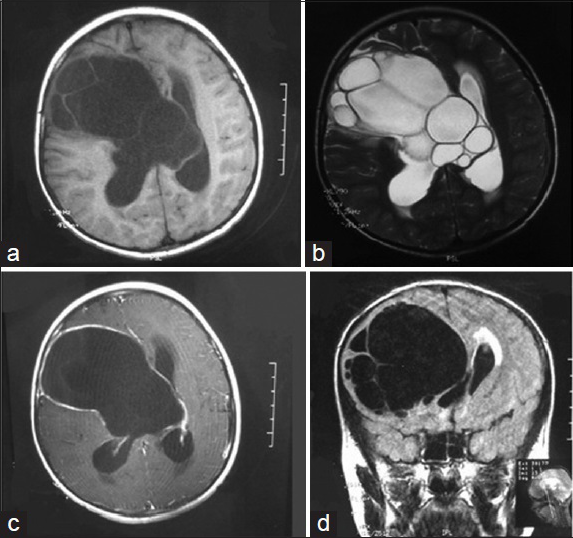

Khan et al from Pakistan presented a rare case with multiple cerebral hydatid cysts. The discussion is an excellent review of the treatment of this disease rarely seen in the developed world. See figure 1 in the sidebar above.